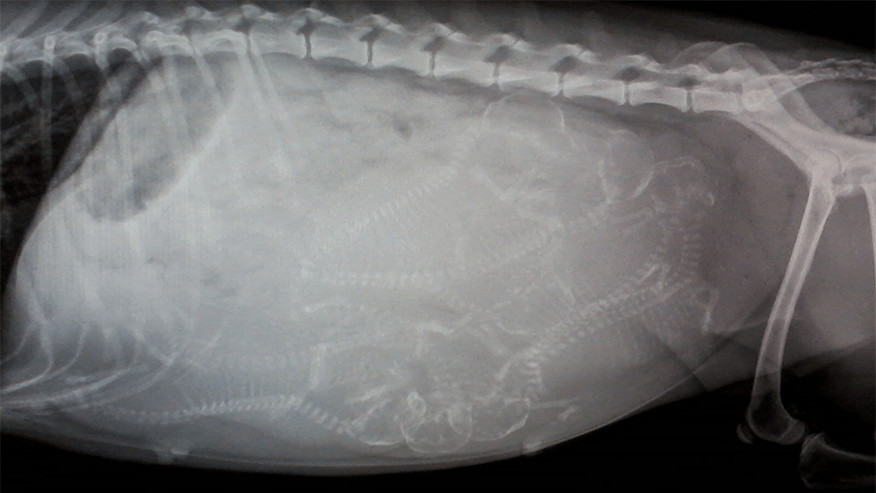

• Our hospital offers a number of diagnostic imaging services. Diagnostic imaging refers to the techniques and processes used to create images of your pet's body or body parts for medical purposes. .... Read more

• Our hospital is proud to offer state-of-the-art digital radiology services. Digital x-rays are essentially film-less x-rays. Traditional x-rays use photographic film to capture images whereas digital x-rays use a digital image capture device (computer) to record the x-ray image.... Read more